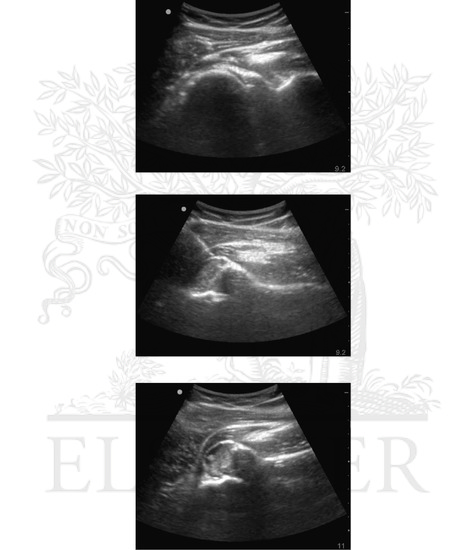

Ultrasound of normal (A) and anteriorly dislocated (B and C) shoulder joint